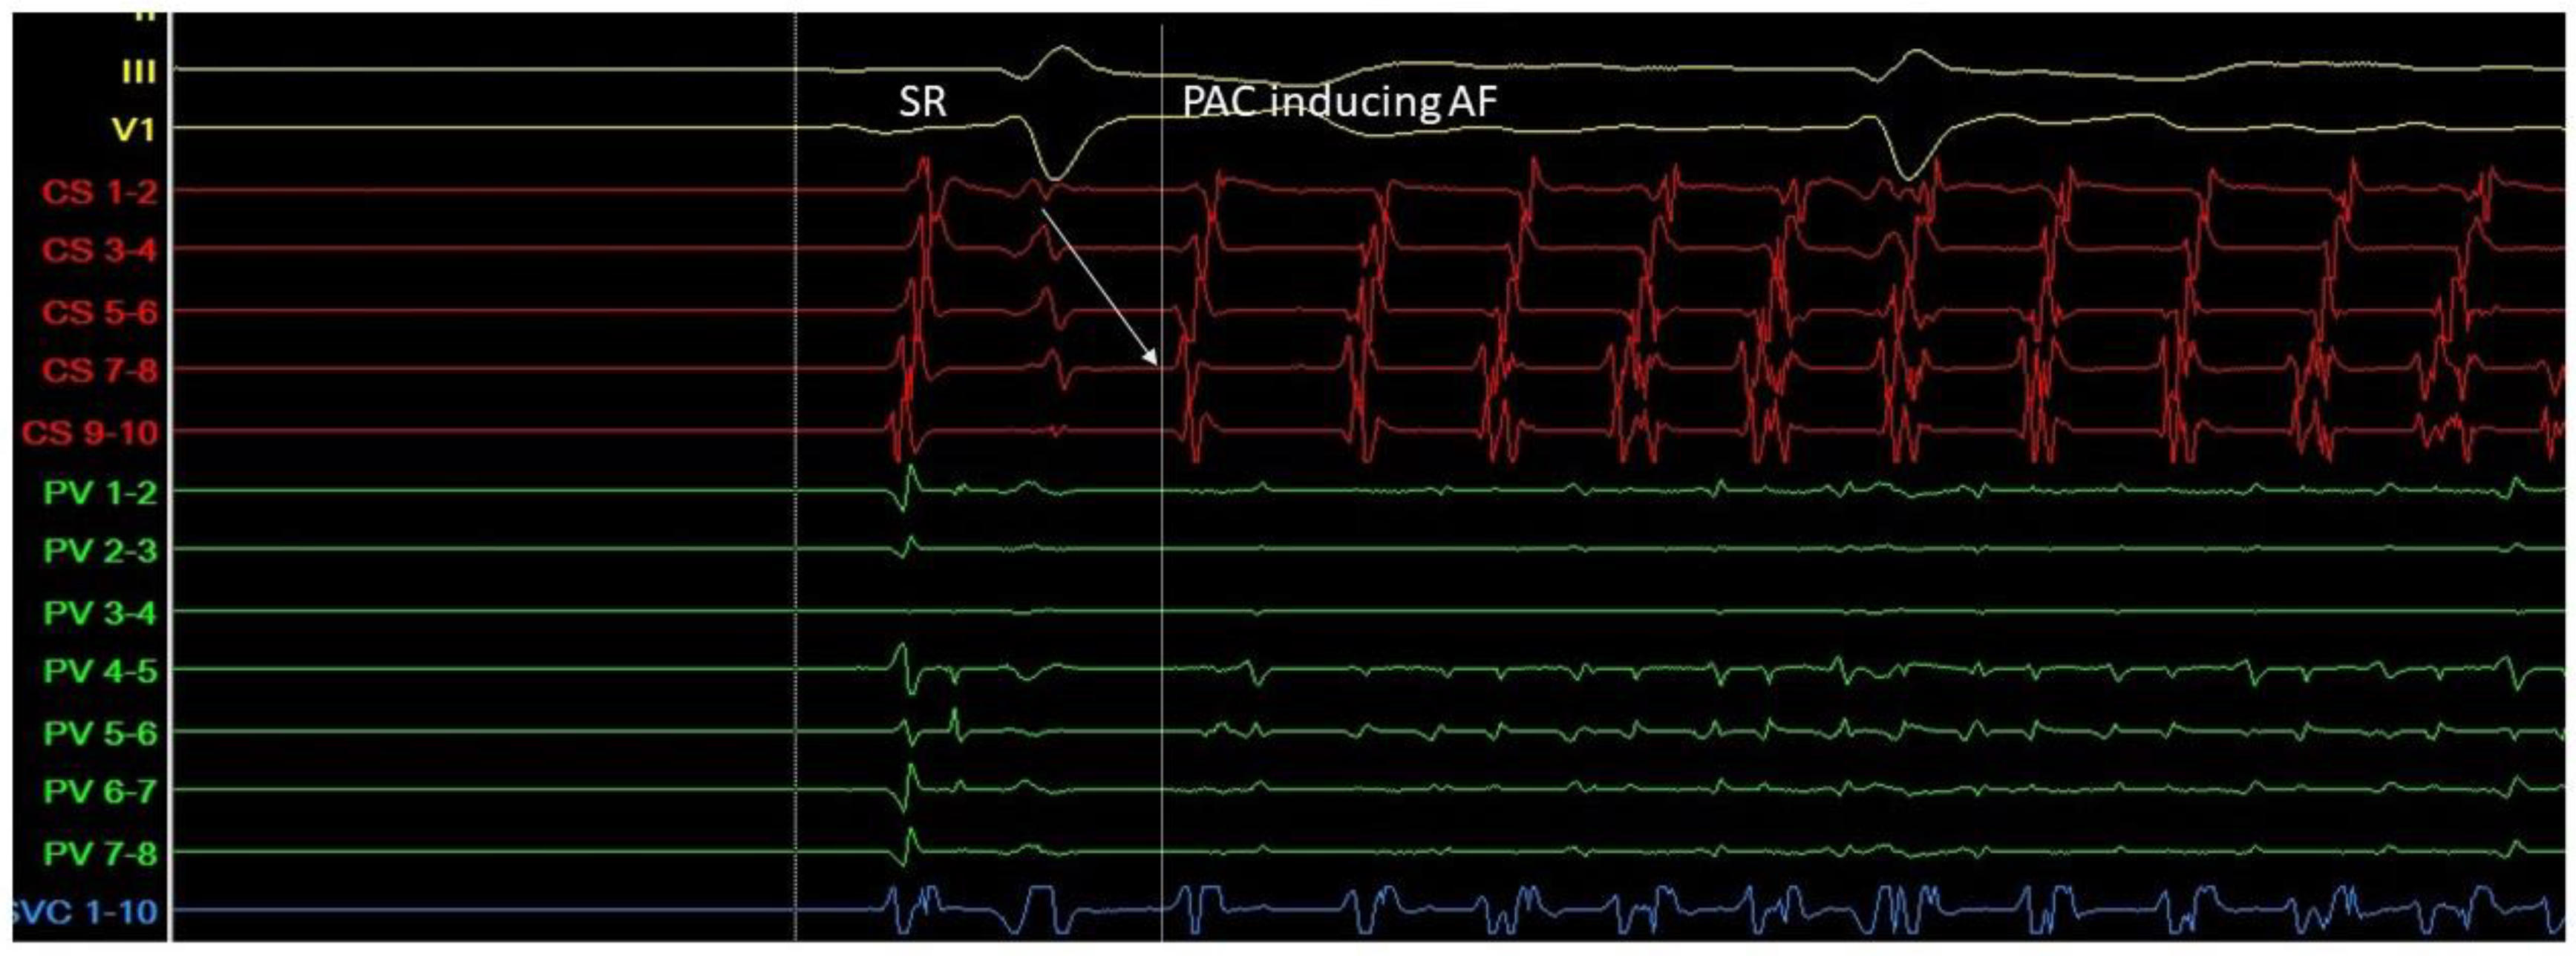

2. Triggers